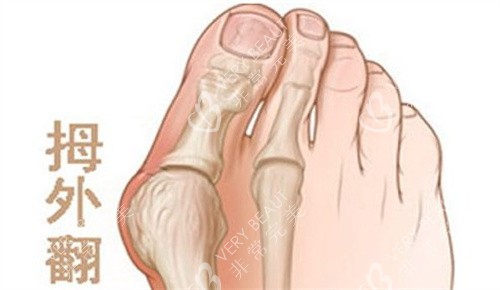

咱先说说,不少做了拇外翻手术的朋友,本来想着术后能踏踏实实走路,结果半年过去了,脚趾还是没劲儿,走两步就疼得慌,心里别提多着急了 —— 这到底是咋回事?是不是手术没做好?别瞎琢磨!今天就请医生把常见原因拆解开,再教你咋自查,帮你把问题根源找出来,咱也好对症解决。

第二个原因:瘢痕粘连 “卡” 住了关节

手术伤口长好后,可能会形成瘢痕,要是瘢痕跟周围的组织粘在一起,就会 “卡” 住脚趾关节,让关节活动不灵活。

关节动不了,走路时脚趾没法正常发力,自然又无力又疼。

自查方法:摸一摸手术伤口周围的皮肤,看看有没有硬邦邦的疙瘩(就是瘢痕),再轻轻活动脚趾,要是感觉有东西拽着、活动受限,可能就是瘢痕粘连了。